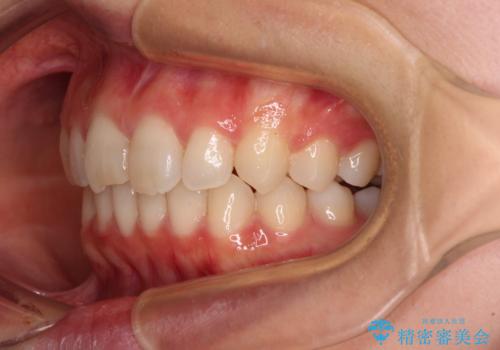

上下ともにデコボコの程度は著しいものではなく、インビザラインで十分に対応可能な歯列不正でした。

後戻りによりスペースができてしまうことを避ける目的で、IPR(歯と歯の間を削る)を極力用いない矯正治療を行うこととしました。